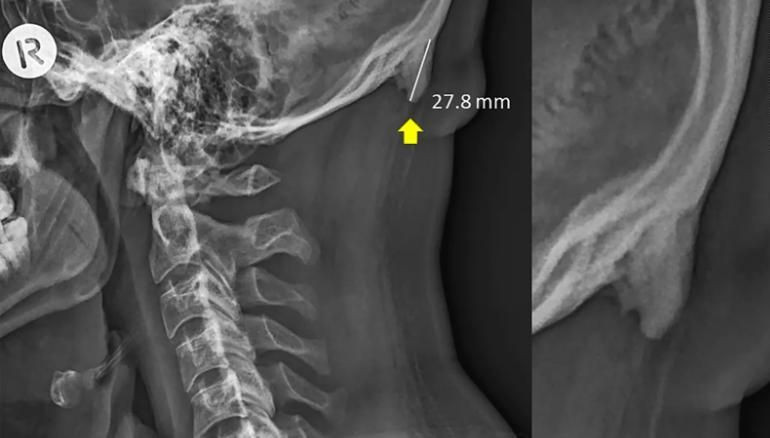

ภาพเอกซเรย์ฐานกระโหลกส่วนท้ายทอยที่มีกระดูกงอก กลายเป็นไวรัล หลังนักวิจัยออสเตรเลียอ้างว่าเกิดจากพฤติกรรมใช้มือถือมากไป

พวกเขาจึงตั้งสมมติฐานว่าเหตุที่กระดูกท้ายทอยที่มีขนาดใหญ่กว่าปกติเหล่านี้มาจากพฤติกรรมการก้มหน้ามองจอโทรศัพทย์มือถือที่เราทำในชีวิตประจำวันจนส่งผลให้ปุ่มนอกของท้ายทอย หรือที่เรียกว่า external occipital protuberance (EOP) เปลี่ยนแปลงไปตามพฤติกรรมและสรีระของร่างกาย